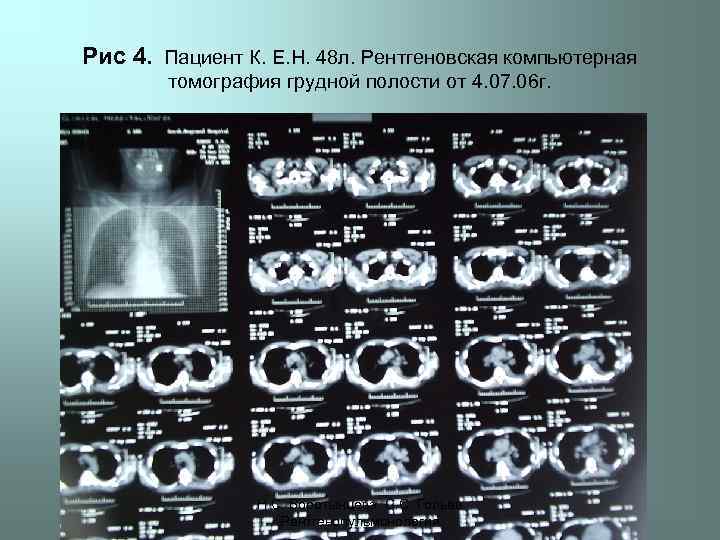

Рис 4. Пациент К. Е. Н. 48 л. Рентгеновская компьютерная томография грудной полости от 4. 07. 06 г. Н. С. Воротынцева. С. С. Гольев Рентгенопульмонология